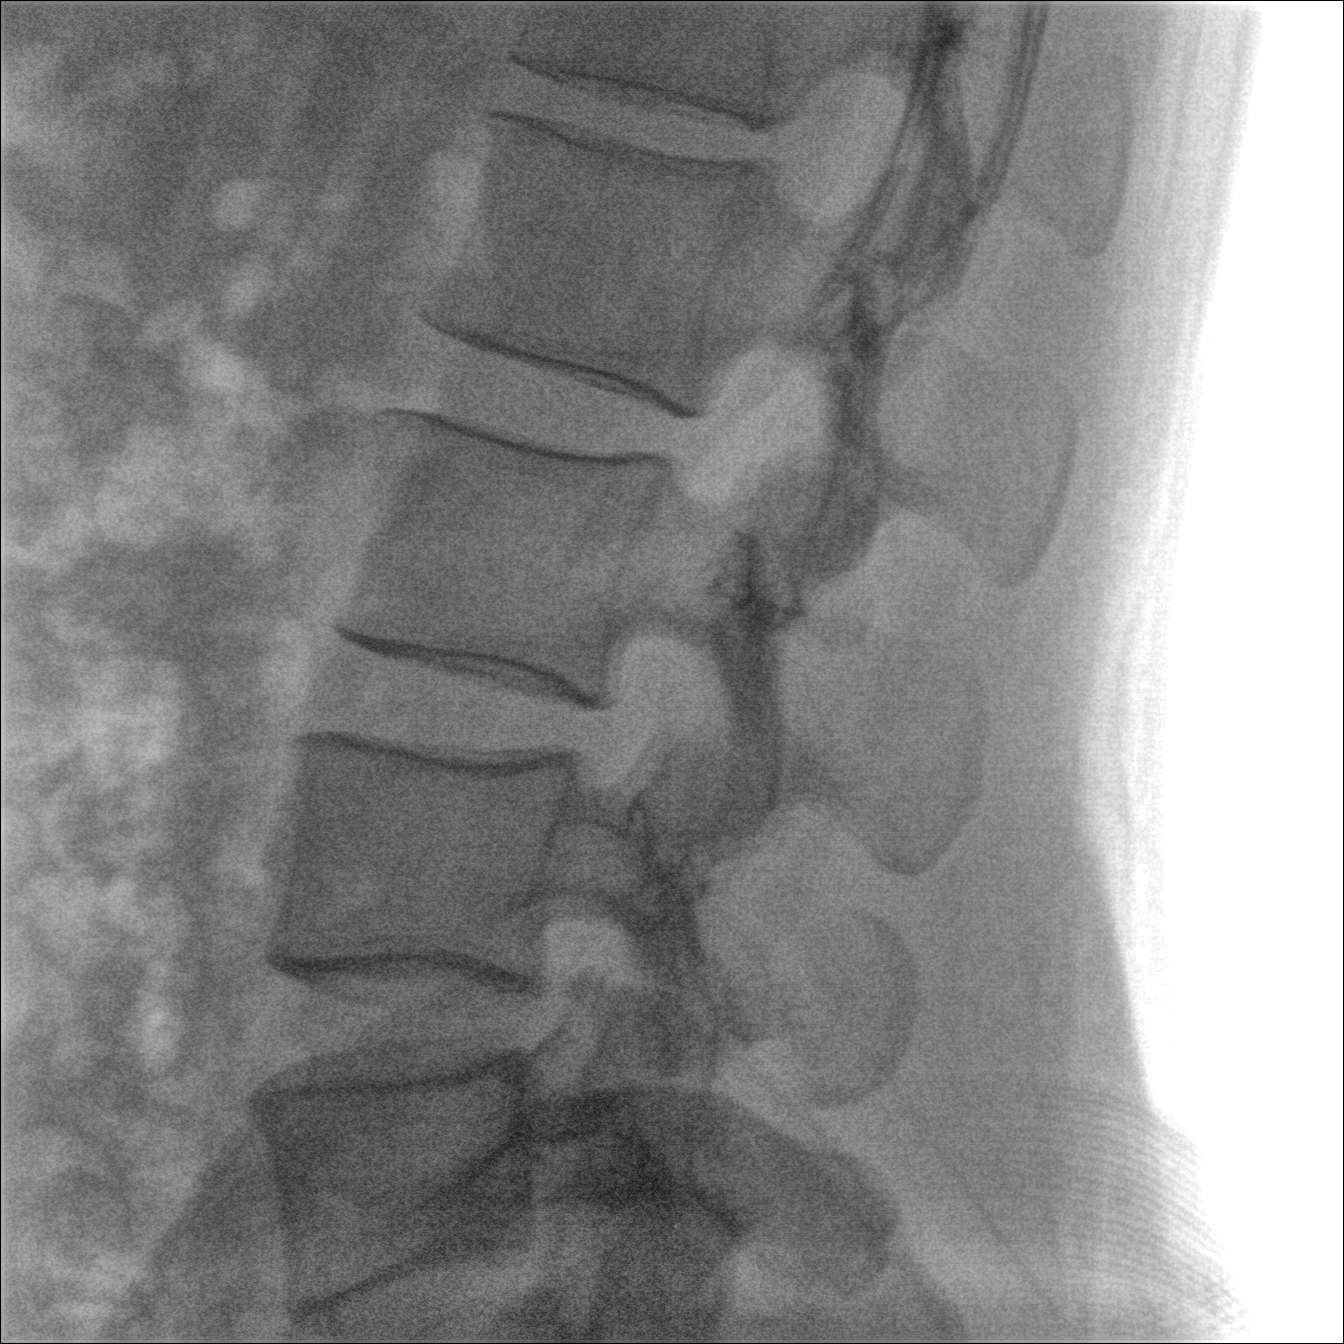

配備了兩種平板尺寸,大尺寸動(dòng)態(tài)平板探測(cè)器成像面積較傳統(tǒng)平板探測(cè)器提升了25%以上,在視野需求大的手術(shù)中,便于醫(yī)生更好定位病灶點(diǎn),規(guī)劃手術(shù)方案,減少因視野范圍不足而多次透視、點(diǎn)片造成的不便,不僅提高了手術(shù)效率,也減少了輻射劑量。